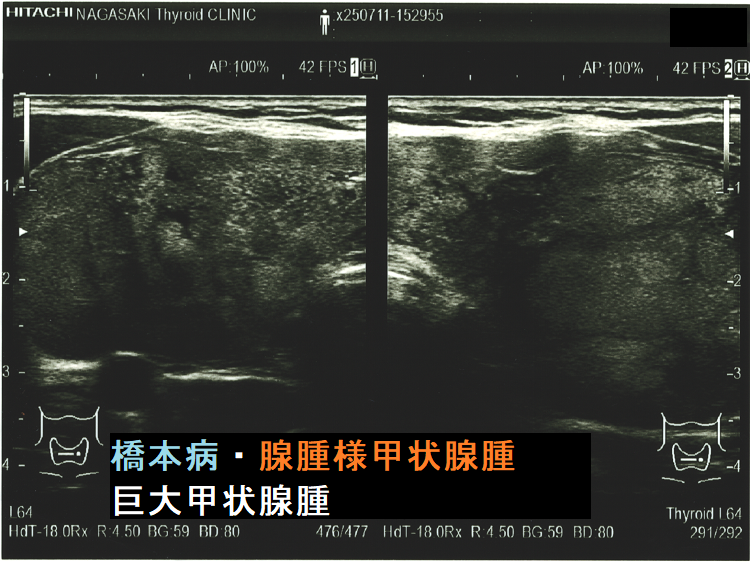

ケース④ 橋本病を基盤とする腺腫様甲状腺腫(気管・食道圧排)

橋本病を基盤とする腺腫様甲状腺腫(気管・食道圧排) 矢状断;等エコーなので甲状腺悪性リンパ腫が隠れているようには見えないが、潜在性甲状腺癌(甲状腺ラテント癌)が存在する可能性は否定できない。かなり気道圧迫している。

ケース⑤ 橋本病を基盤とする腺腫様甲状腺腫・巨大甲状腺腫(気管・食道圧排)